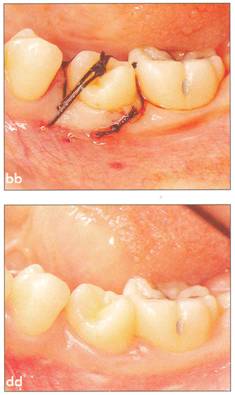

Fi 545e45f g 5-8cc After transplantation. Fi 545e45f g 5-8dd One week after transplantation. |

Fi 545e45f g 5-8ee Six weeks after transplantation. Fi 545e45f g 5-8ff Clinical view 6 weeks after trans plantation |

Fi 545e45f g 5-8gg Three months after transplantation. Inflammatory root resorption is ob. served on the distal aspect of the donor tooth. Root canal therapy was started immediately. Fi 545e45f g 5-8hh One month after temporary obturation with calcium hydroxide. Arrest of root resorption was confirmed and orthodontic treatment was started. |